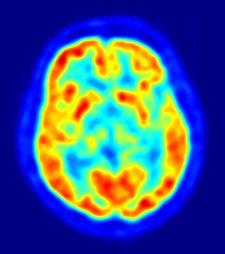

Identifican variantes genéticas asociadas a la enfermedad de Alzheimer

MADRID, 4 Abr. Europa Press -. Dos estudios de las universidades de Pensilvania en Filadelfia (Estados Unidos) y Cardiff en Reino Unido respectivamente han conseguido identificar cinco nuevas variantes genéticas asociadas con la enfermedad de Alzheimer. Los trabajos se publican en la edición digital de la revista 'Nature Genetics'.La enfermedad de Alzheimer, la forma más común de demencia, es un trastorno neurodegenerativo con una alta prevalencia entre los mayores.

Los científicos, dirigidos por Gerard Schellenberg desde Estados Unidos, informan de un estudio de asociación amplia de genoma sobre la enfermedad de Alzheimer en su inicio avanzado que incluyó a 8.309 casos y 7.366 controles cognitivamente normales.El equipo de Julie Williams desde Reino Unido combinó análisis de cuatro estudios de asociación amplia de genoma sobre la enfermedad publicados con anterioridad.A través de los análisis de replicación en los grupos de datos combinados y adicionales, ambos estudios en conjunto informan de cinco nuevas localizaciones asociadas con la enfermedad de Alzheimer.Esto eleva a 10 el número de localizaciones de susceptibilidad confirmadas para la enfermedad de Alzheimer y en conjunto incluyen genes candidatos con implicaciones en el funcionamiento inmune, procesos en las membranas celulares y el procesamiento de los lípidos.Los trabajos así subrayan mecanismos moleculares que podrían estar implicados en la neurodegeneración y la eliminación en el cerebro del amiloide beta, el principal constituyente de las placas amiloides que se forman en el cerebro y que caracterizan a la enfermedad de Alzheimer.Sigue a Europa Press Salud en Twitter: @EP_SaludSomos información